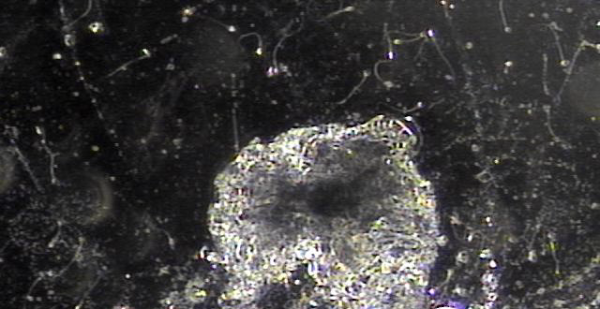

전립선과 정낭, 사정관,전립선관,정관등의 표적 치료후 치료된 상피세포덩어리의 현미경학적 자료입니다.

This microscopic image shows clusters of dead or damaged epithelial cells that were successfully removed through targeted treatment of the prostate, seminal vesicles, ejaculatory ducts, prostate ducts, and vas deferens.